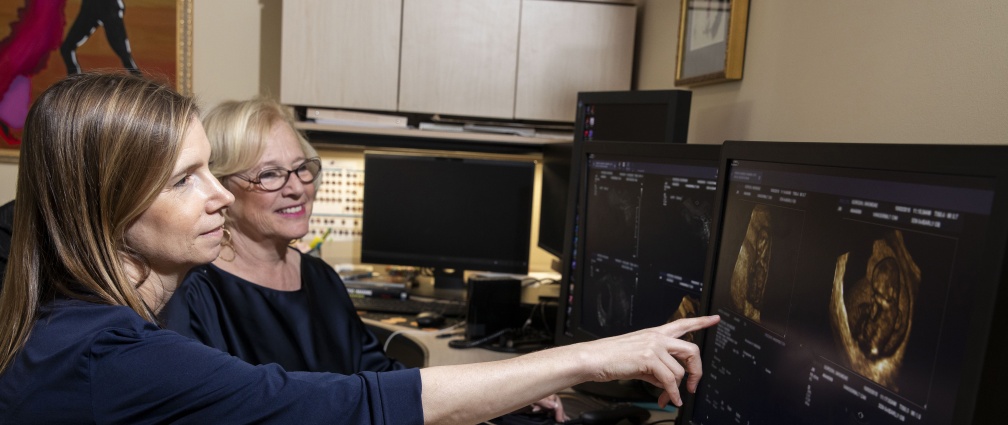

The Vanderbilt Center for Women's Imaging (CWI) is a facility dedicated to ultrasound that primarily serves obstetric and gynecologic patients. Annually, CWI performs more than 33,000 exams that are viewed in real time by radiologists who provide immediate reports at the time of the patient’s exam.

First trimester sonograms, nuchal translucency measurements as a component of both an ultrascreen and instant risk assessment (IRA), fetal anatomy scans, fetal growth and BPP’s are offered for pregnant patients. Pelvic sonograms include 3D reconstruction in all patients, and expertise in the evaluation of patients with a family history of ovarian cancer or BRCA mutation is also provided.